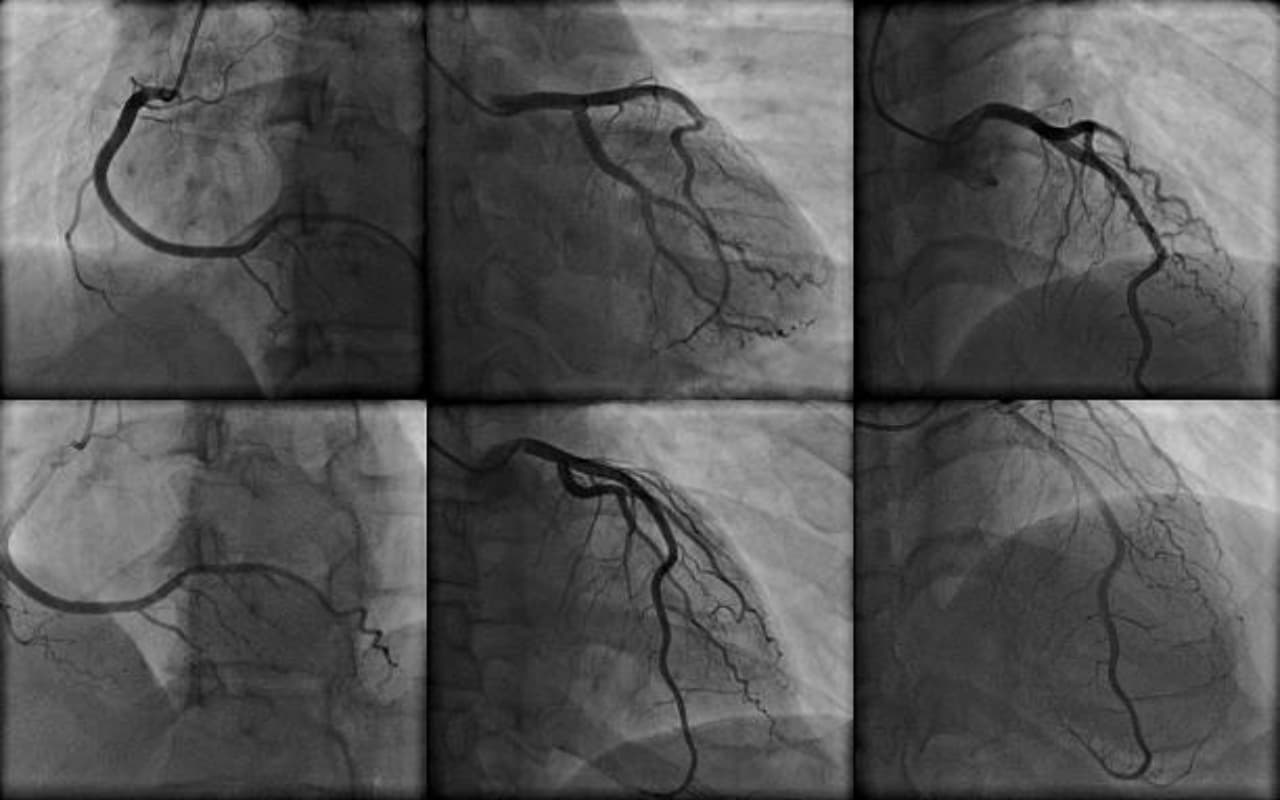

कोरोनरी एंजियोग्राफी : कोरोनरी एंजियोग्राफी का उपयोग कोरोनरी धमनियों में रुकावटों, संकुचन या अन्य समस्याओं का पता लगाने और हृदय की मांसपेशियों में रक्त के प्रवाह की जांच करने के लिए किया जाता है। यह कार्डियोलॉजी में एक महत्वपूर्ण निदान उपकरण है और डॉक्टरों को यह तय करने में मदद करता है कि किस उपचार विकल्प का उपयोग करना है।